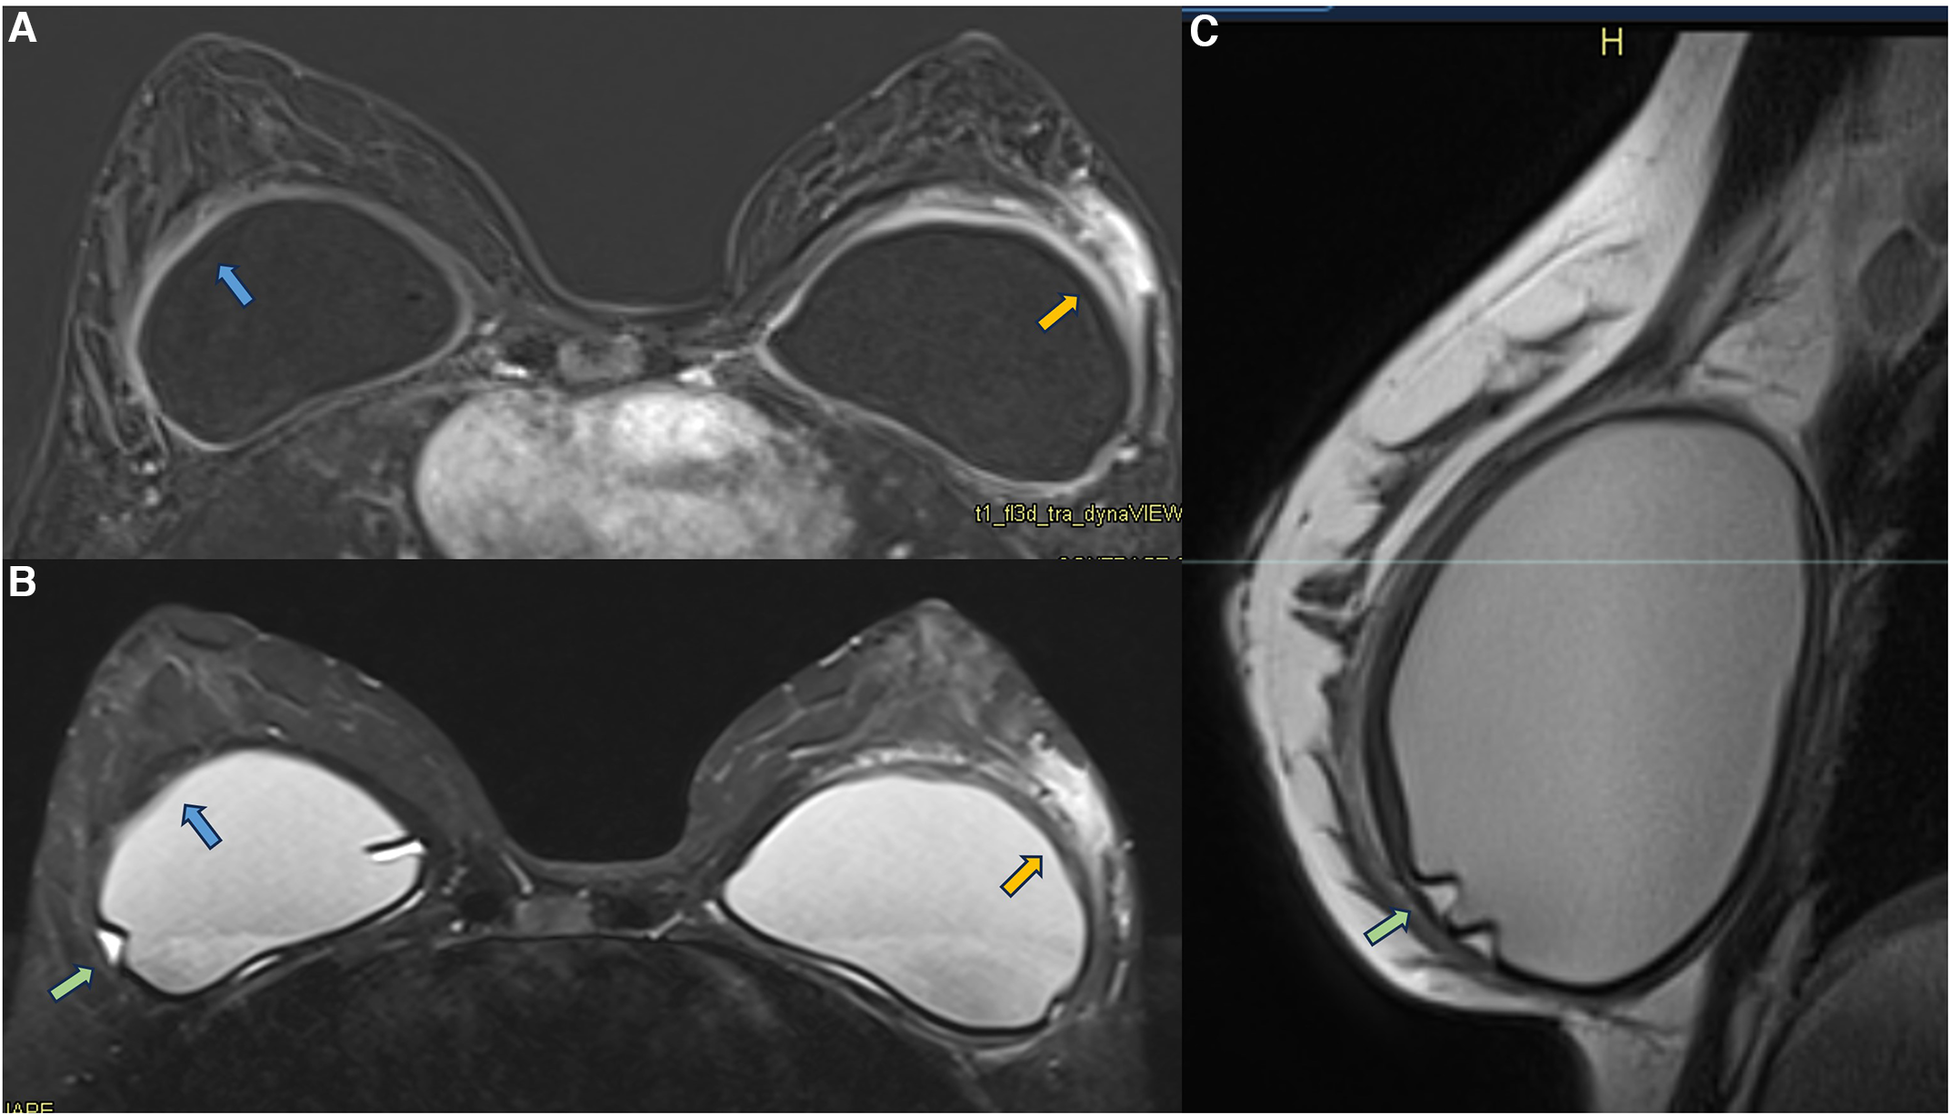

In some cases of patients with symptomatic capsular contracture, who present with clinical signs of breast inflammation, magnetic resonance imaging may show non-mass enhancement of the pericapsular glandular tissue. Non-mass enhancement is a suspicious MRI descriptor finding that should be further investigated. As the foreign body triggers the inflammatory process in the implant fibrous capsule, and due to the evidence of extracapsular migration of silicone particles, there is expected to be an immune reaction in all places with free silicone particles (21, 31, 30, 47) (Figure 9).

Figure 9. A 36-year-old woman with acute left breast swelling with retropectoral implants for 7 years. The axial post-contrast image (A), T2** sequence (B), and sagittal proton density sequence (C) show a loss of the signal homogeneity of the silicone implants associated with intracapsular granulomas (green arrow). The blue arrows show a moderate inflammatory process of the right fibrous capsule in contiguity with the pectoral muscle (blue arrow). The orange arrow shows inflammatory signs of the left fibrous capsule associated with non-mass enhancement of the pericapsular tissue. Thickening of the pectoral muscle is also observed. The biopsy shows mastitis.

Generally, the inflammatory process is self-limited, lasting for about 5 weeks and peaking in intensity in the first 2–3 weeks. Reactive mastitis is the central diagnostic hypothesis, but a differential diagnosis must be employed, and the patient should be forward to a diagnostic biopsy. In these cases, as the differential would be breast carcinoma. These lesions should be classified into category 4 according to the BI-RADS lexicon (lesions suspicious for breast carcinoma).